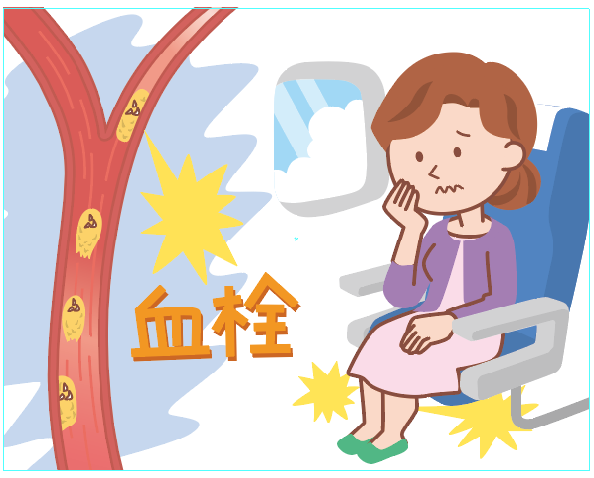

エコノミークラス症候群のイラスト素材29373435- PIXTA。

川崎 静脈血栓塞栓症浅田内科・循環器内エコノミークラス症候群。

エコノミークラス症候群広島の調剤薬局 FINE PLUS まえだ薬局・プラス薬局 のブログ。

4 エコノミークラス症候群 肺血栓塞栓症 に関するQ&A - 4 エコノミークラス症候群 肺血栓塞栓症 に関するQ&A -災害時の対応について一般社団法人日本呼吸器学会。

エコノミークラス症候群病気と治療の検索サイト「メディカルブレイン」。

肺血栓塞栓症・エコノミークラス症候群 男性 のイラスト – フリーイラスト素材集 KuKuKeKe。

エコノミークラス症候群震災時に起こりやすい健康問題と予防法 1看護roo! カンゴルー。

4 エコノミークラス症候群 肺血栓塞栓症 に関するQ&A - 4 エコノミークラス症候群 肺血栓塞栓症 に関するQ&A -災害時の対応について一般社団法人日本呼吸器学会。

4 エコノミークラス症候群 肺血栓塞栓症 に関するQ&A - 4 エコノミークラス症候群 肺血栓塞栓症 に関するQ&A -災害時の対応について一般社団法人日本呼吸器学会。

エコノミークラス症候群 深部静脈血栓症 メカニズムのイラスト素材29374549- PIXTA。

エコノミークラス症候群:入院中に死亡8件 医療事故調査毎日新聞。